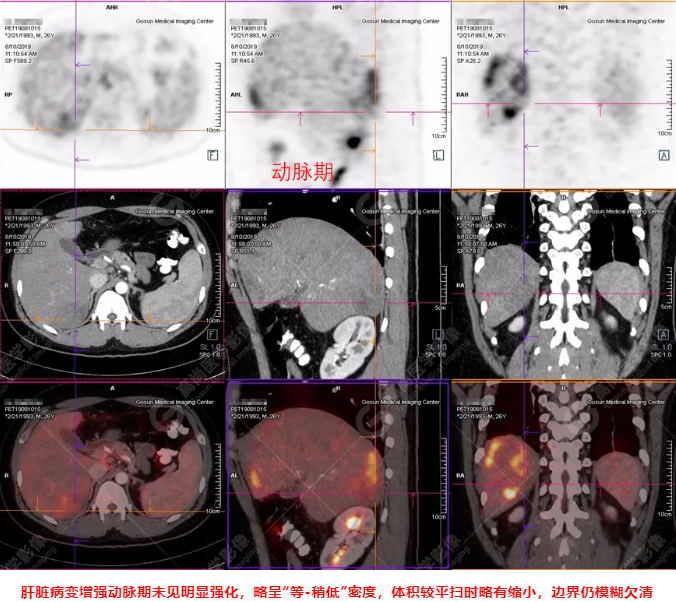

B超及CT檢查發(fā)現(xiàn):肝臟多發(fā)低密度占位。

PET/CT全身圖

PET/CT診斷

嗜酸性粒細(xì)胞增多癥肝浸潤